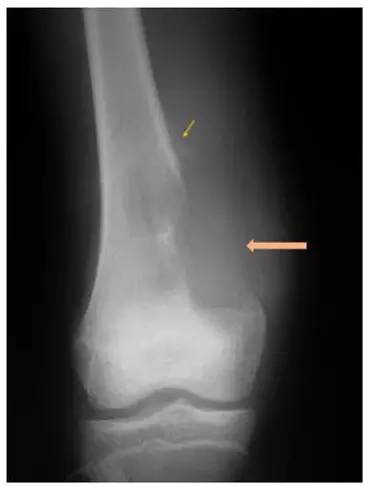

儿童骨肉瘤图片

儿童骨肉瘤图片,儿童骨肉瘤好发部位

儿童骨肉瘤好发部位

骨肉瘤图片

骨肉瘤x线

骨肉瘤影像学